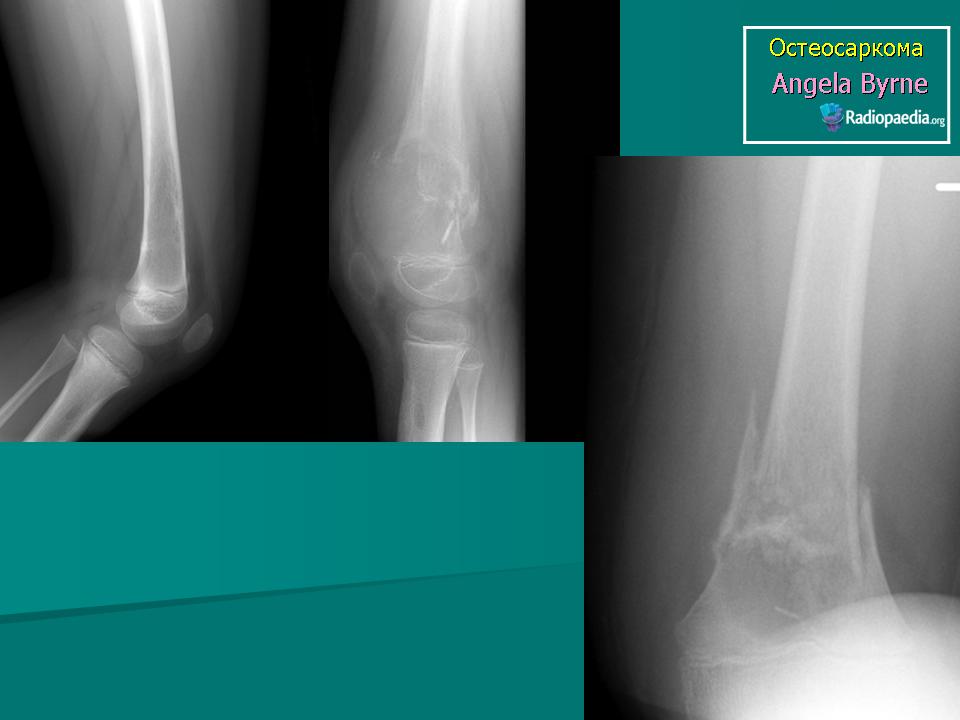

Рентгенологическая картина остеогенной саркомы кости - 98 фото